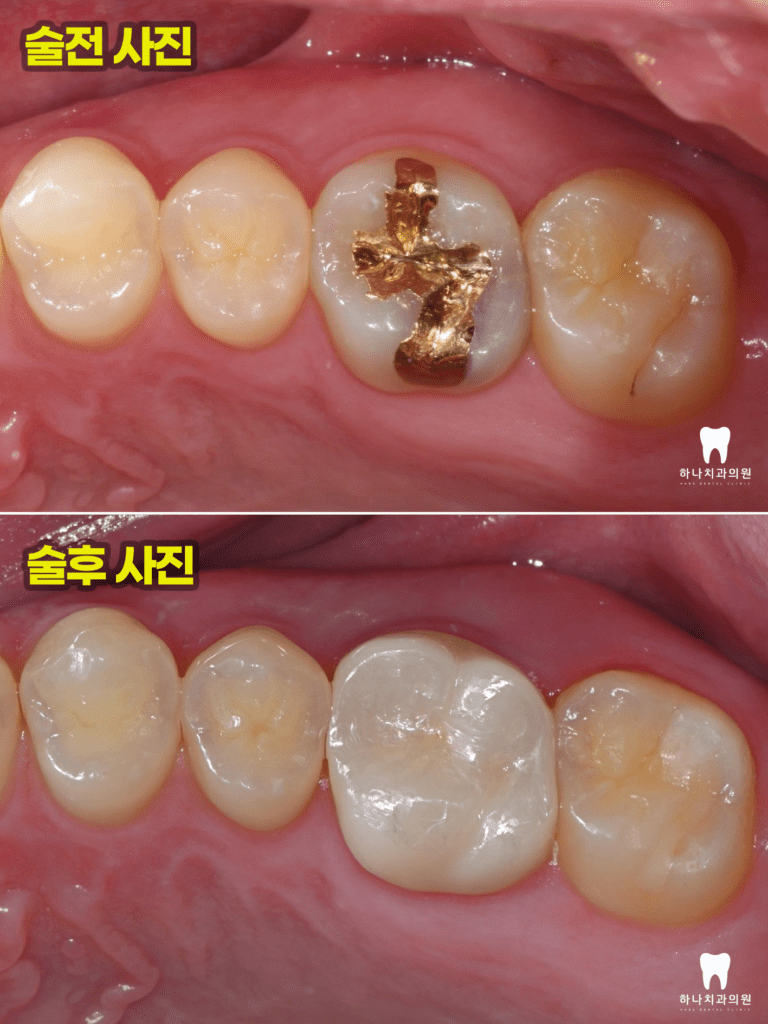

위 환자분께서는 30대 남성분으로

신정동치과 하나치과

홈페이지의 증례와 사례를 보고

스케일링과 검진을 위해 내원해 주셨습니다.

전체 x-ray 촬영 시 왼쪽 위 첫 번째 어금니에

까맣게 충치로 보이는 투과상을 발견하였는데요.

환자분께서는 불편함을 느끼지 않으셨지만

해당 인접면 우식을 해결하지 않는다면

순식간에 치아를 망가뜨릴 수 있는

부위임을 설명드리고 치료를 조심스럽게

권유 드렸습니다.

우식의 크기로 보았을 때

신경치료의 가능성을 배제하기에는

어려움이 있었지만 우식 부위 제거,

코어, 크라운으로 기능을 회복할 수 있도록

계획을 수립하였습니다.

모든 치료를 마치고 난 후,

4년 뒤에도 전혀 문제를 발견할 수

없었고 주변 자연 치질과 조화로운 잇몸

기능을 유지하고 있는 것을 관찰하였습니다.